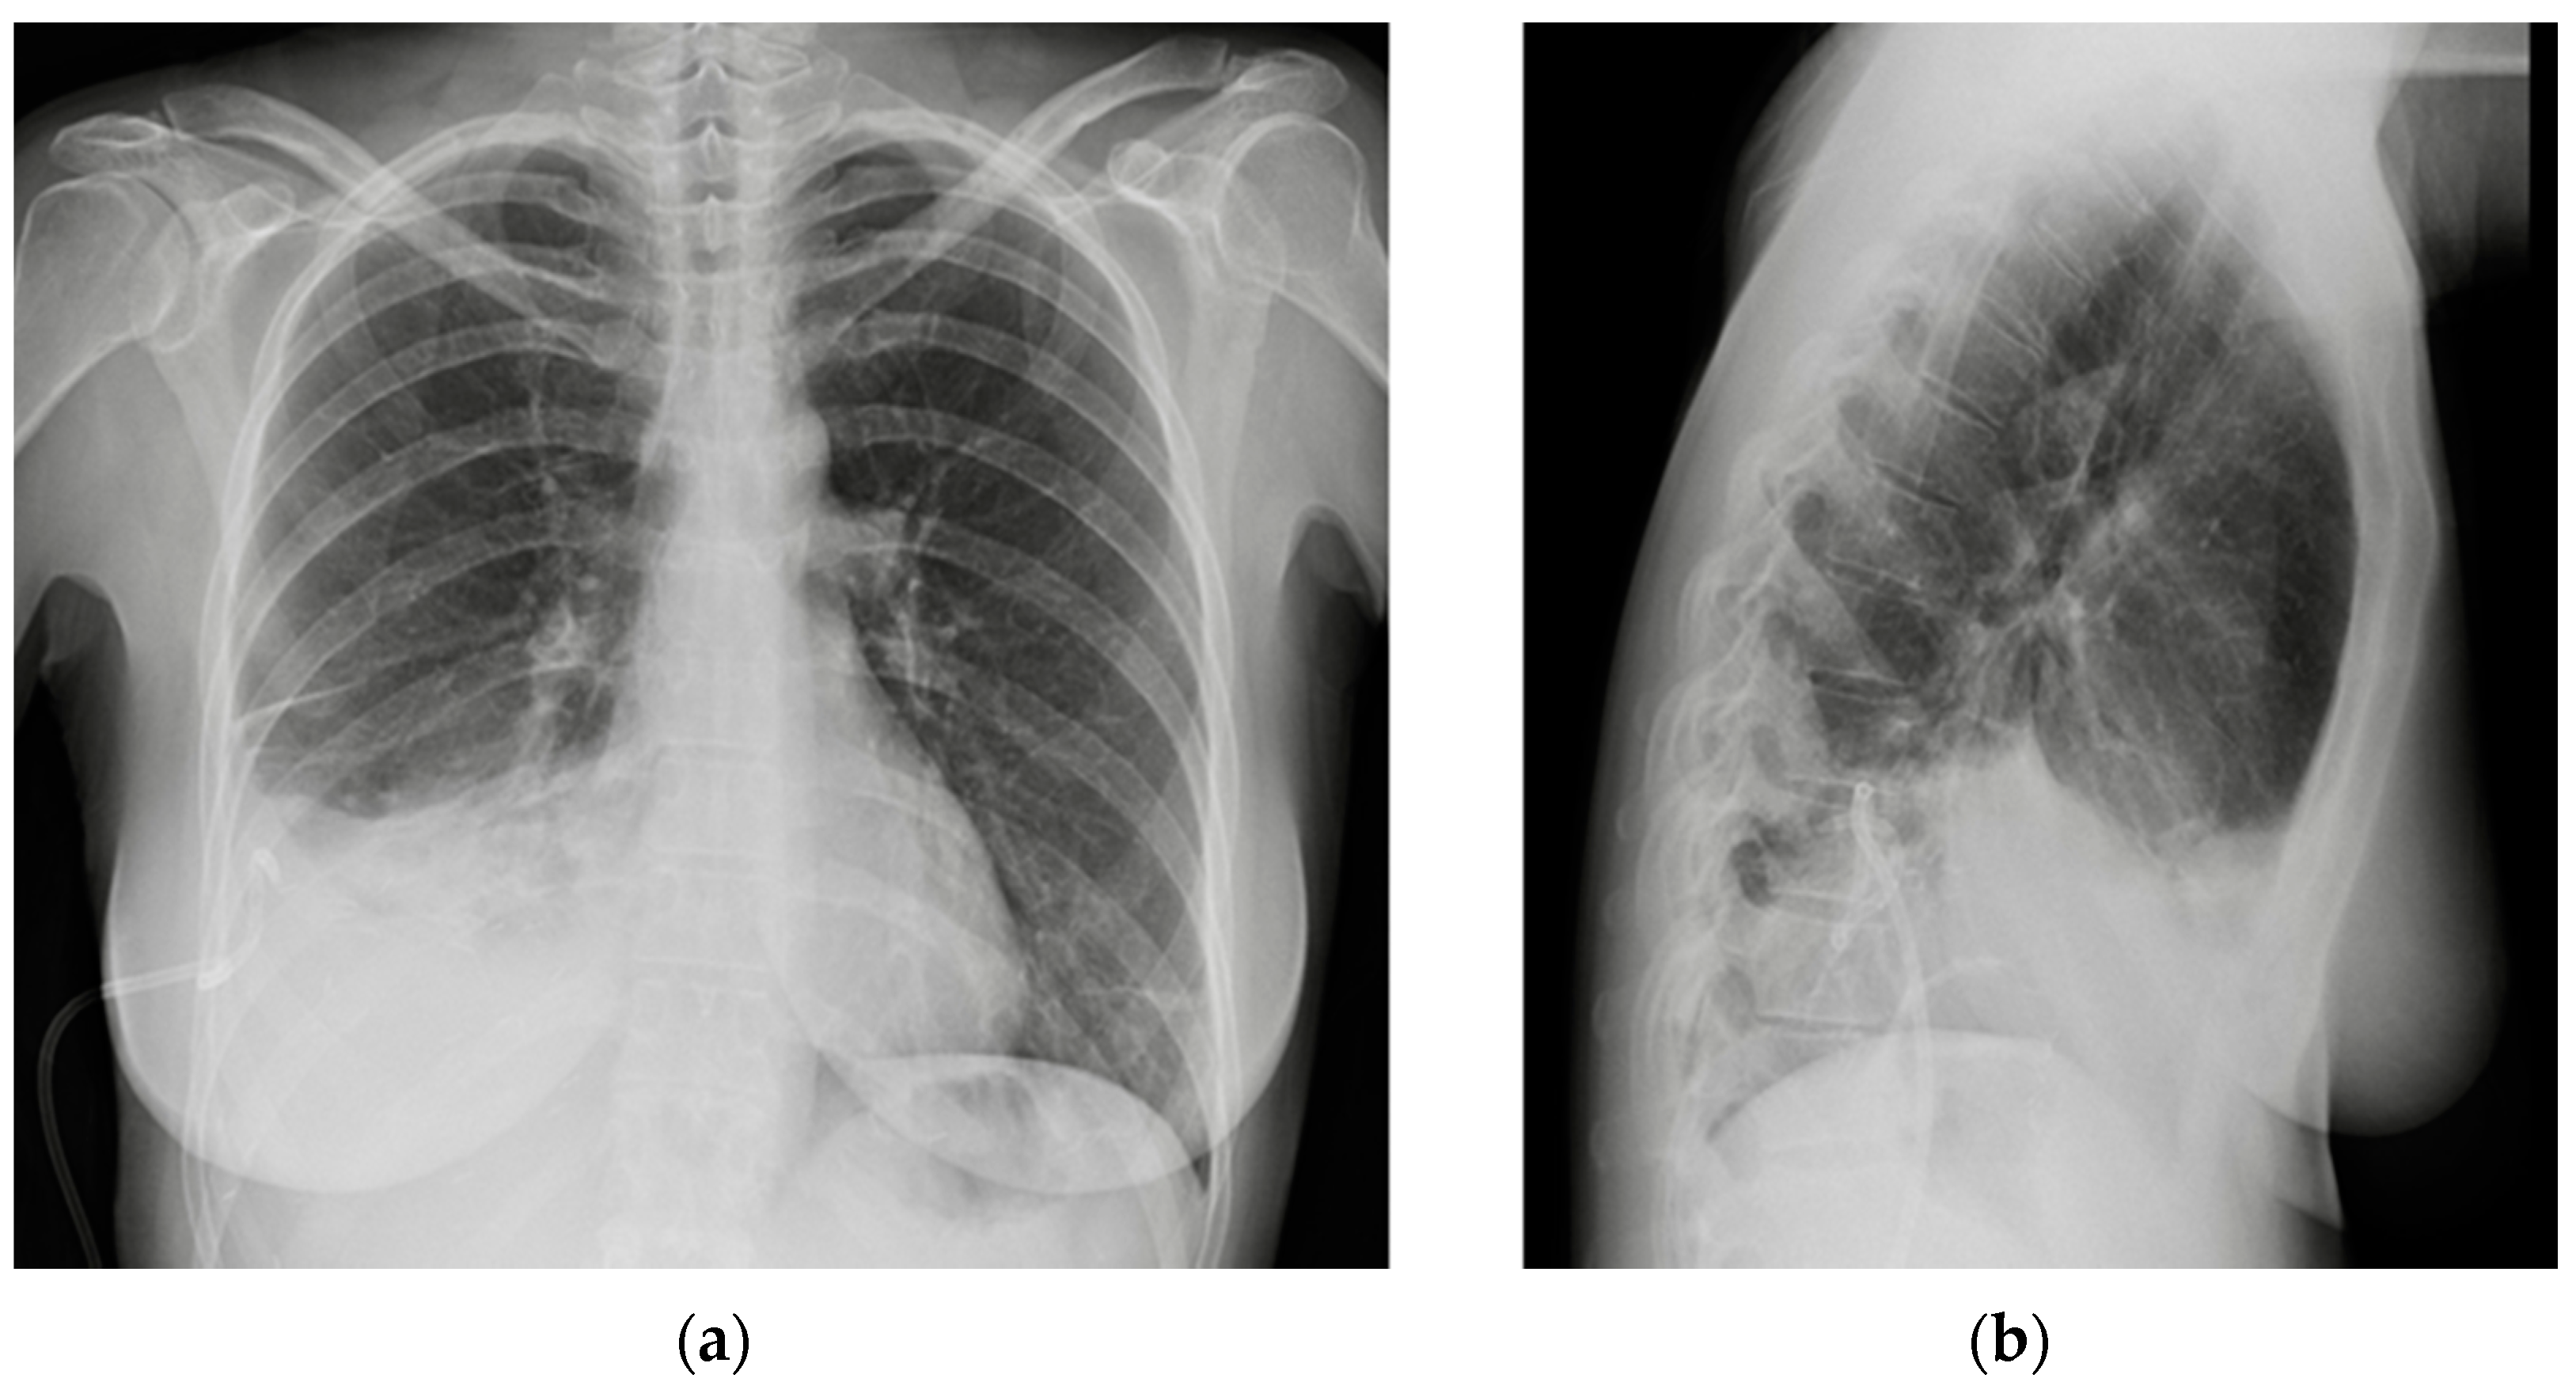

Figure 19.

Coronary artery stents (red arrows), barely visible on the PA projection (a), can be better appreciated on the LL view (b).